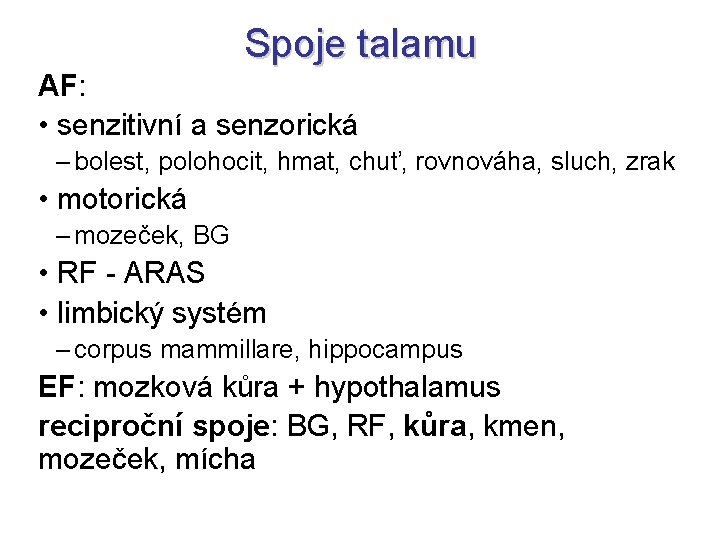

Spoje talamu AF: • senzitivní a senzorická – bolest, polohocit, hmat, chuť, rovnováha, sluch, zrak • motorická – mozeček, BG • RF - ARAS • limbický systém – corpus mammillare, hippocampus EF: mozková kůra + hypothalamus reciproční spoje: BG, RF, kůra, kmen, mozeček, mícha